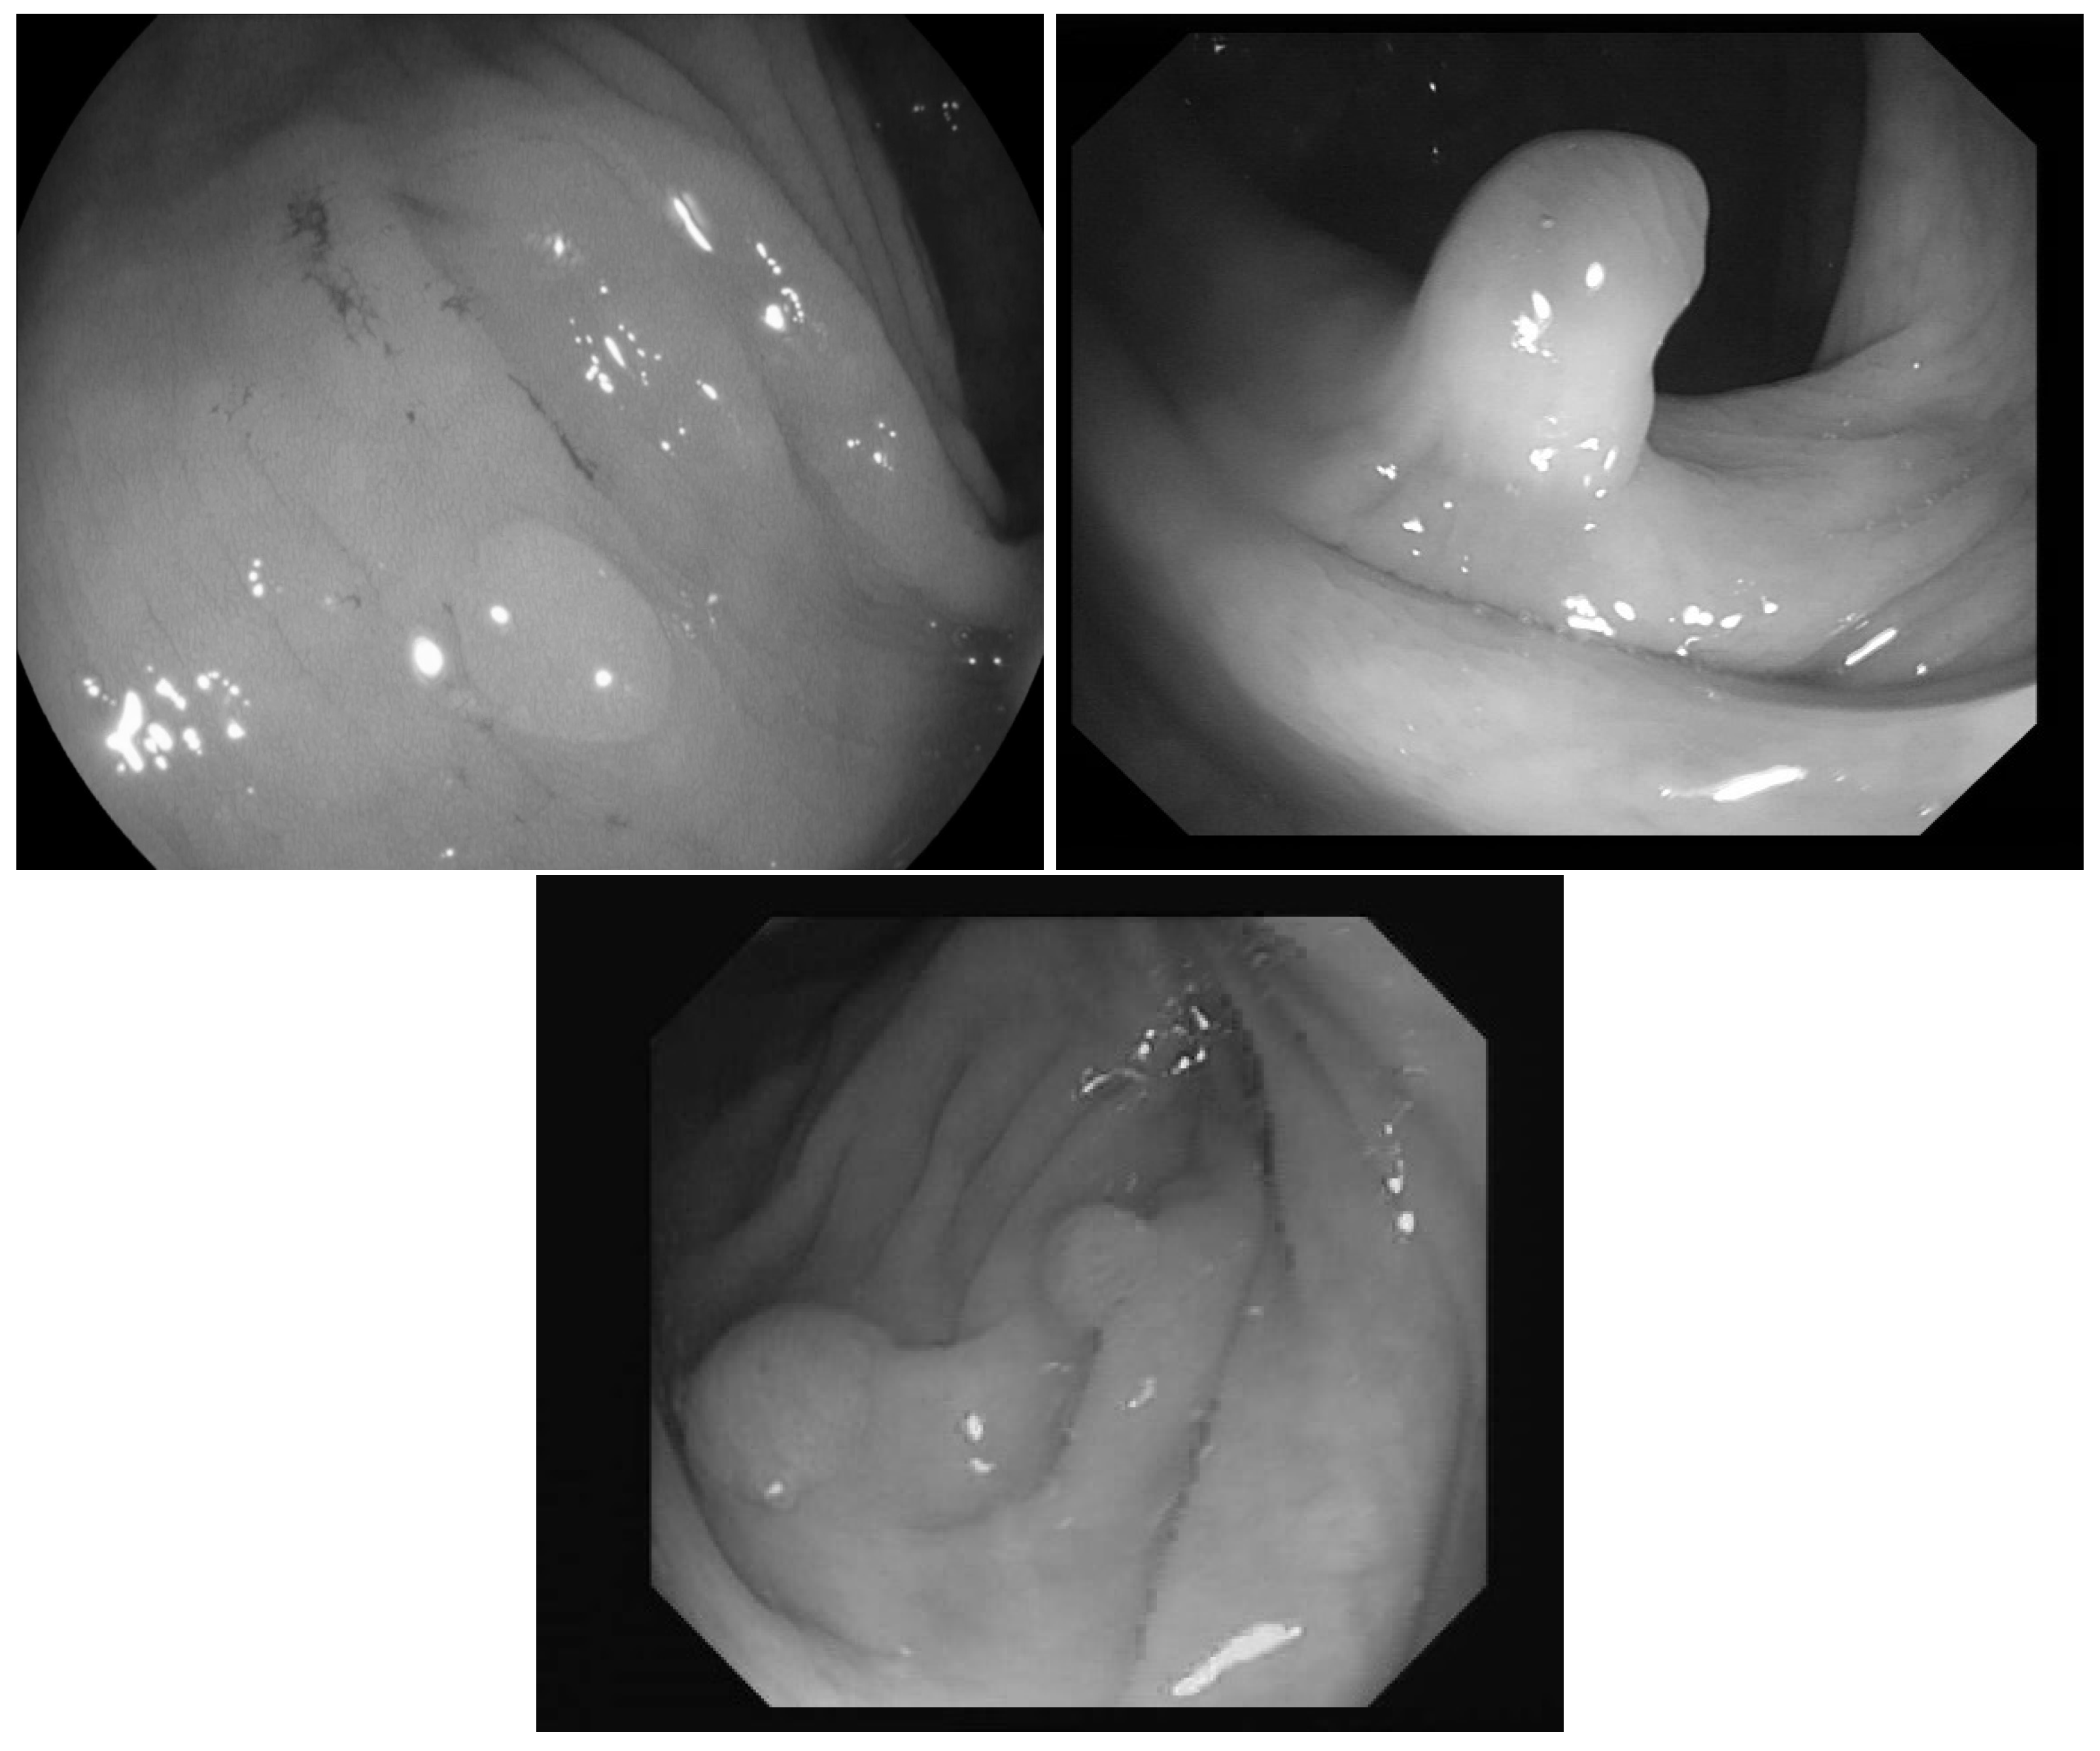

In [23] the images were classified into three classes based on the angle of the view of the polyp: zenithal, lateral, and semilateral, see Figure 1. In the zenital case, the polyps can be seen in a top view, from this view they are not significantly lighter than the environment, but their circumference and the surface texture are usually well distinguishable. A polyp when viewed from its side (i.e., from a lateral view) with a much darker–distant and therefore, worse lit–bowel wall background. Then there is also an intermediate semilateral view. In this case, the background is somewhat darker than the polyp but often the contour, especially at the polyp’s base’ is hardly visible.

Figure 1. Sample pictures from widely used colorectal image-bases [13,23,24]. The left image shows the zenithal view of a colorectal polyp, the second one is a lateral view, while the third is a semilateral view. The resolution differences of the three databases are also visible on the images.